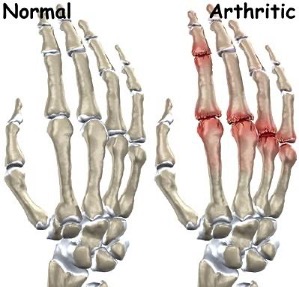

When cartilage is worn or damaged by age, trauma, illness, or infection over time, the bones rub against each other. As a result, they progress to a degenerative state. The result is unbearable pain as both ends of the bone wear away – known as arthritis.

- Osteoarthritis – Osteoarthritis, the most frequent form of arthritis, is a consequence of the erosion and breakdown of cartilage that covers bones due to aging and years of use.

- Rheumatoid Arthritis – Rheumatoid Arthritis is a relentless inflammatory disorder that brings aches, rigidity, and inflammation to its victims. The autoimmune condition typically manifests in multiple joints on both sides. Invariably, it is caused when the body’s natural defense mechanism mistakenly targets healthy tissue instead of foreign invaders.

- Post-Traumatic Arthritis – Post Traumatic arthritis is a type of joint inflammation that can be linked to trauma or injury. While similar in many ways to osteoarthritis, posttraumatic arthritis usually occurs suddenly and has an identifiable cause, like a fractured bone caused by an accident.